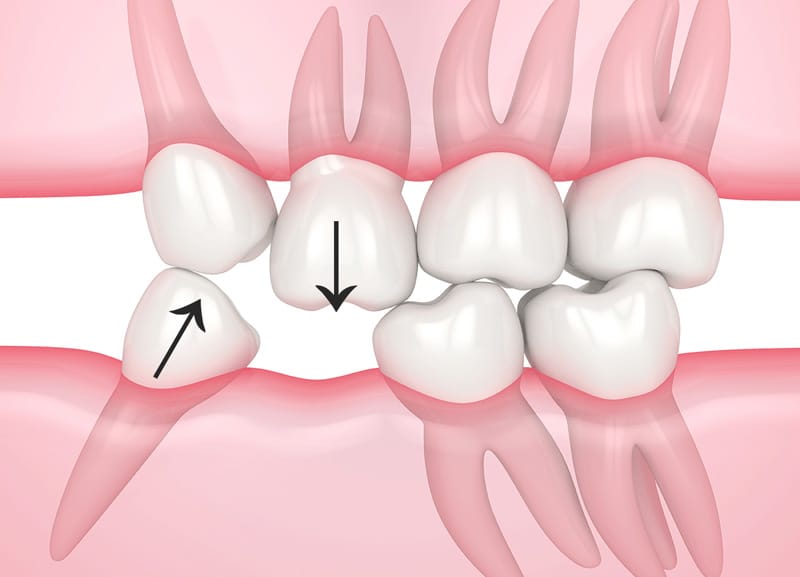

Răng kế cận nghiêng đổ, xô lệch

Răng đối diện trồi xuống

Tác hại mất răng số 6